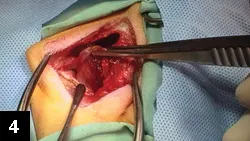

Figure 4. Elevation of the internal obturator flap from the ischial table.

Surgical correction of perineal herniation is standard. The defect may be closed primarily by apposing separated muscles (Figure 3.). Because this is often insufficient, the most common method of repair is muscle transposition using the internal obturator as a muscle flap (Figure 4.). To close the herniation, the internal obturator muscle is elevated off the floor of the ischium, rotated, and then secured medially (often to the external anal sphincter), dorsally, and laterally (Figure 5.).